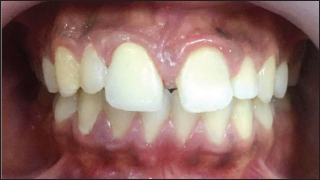

Management initiated with removal of metal-ceramic crown using a crown remover. Pain management for non-vital immature tooth was done following protocols in accordance to the previous reports through root canal therapy with apexification [4]. As a definitive restoration post endodontic treatment, a metal ceramic crown with a collarless design was given (Figure 3). After 1 year follow-up, gingival inflammation has completely resolved and presented normal form of gingival margin which is thinner and sharper (Figure 4). A periapical radiograph was exposed and it revealed, continuity in lamina dura and consistent width of periodontal ligament space, suggests healing of periapical lesion (Figure 5).

Figure 5.